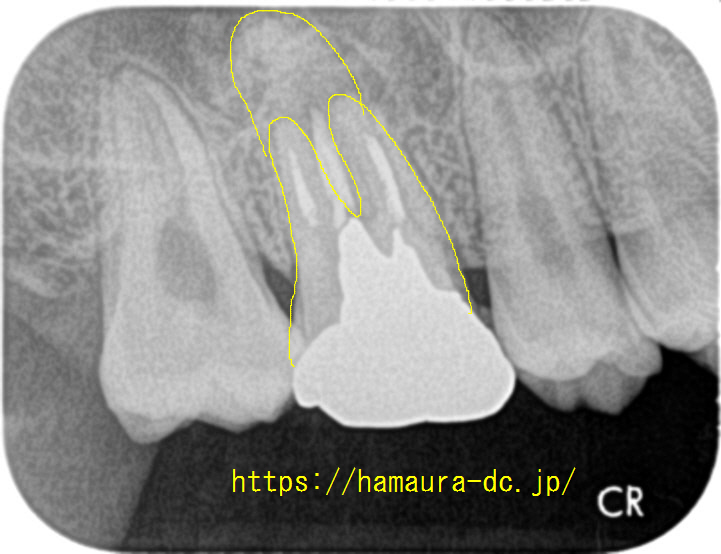

レントゲン写真で確認すると過去に根管治療がされていましたが、根管の一つの処置が不完全に見えます。